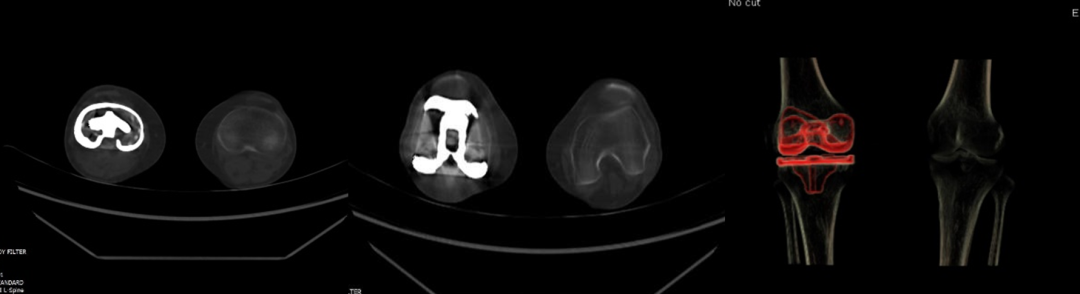

5.去金属伪影:能谱CT单能量成像结合MAR技术可在颅脑成像、颅内动脉瘤夹闭术后及骨关节金属植入术后复查中获得较好成像效果。